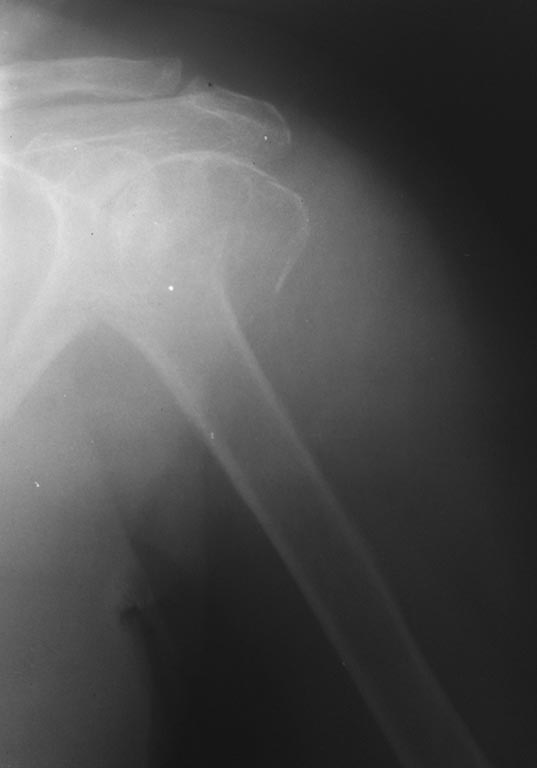

Добрый день, коллеги! Трёхфрагментарный перелом проксимального отдела

плечевой кости (большой бугорок без смещения). Больная 1939 г.р.

сопутствующая патология: ИБС. ПИКС.

Ревматоидный полиартрит. Плюс к данному перелому- перелом шейки

бедра(планируется эндопротезирование). Какой вид остеосинтеза

предпочтительнее? Фиксация винтом большого бугорка винтом через прокол и

напряжённые гамма-спицы, или всё таки пластина? Заранее